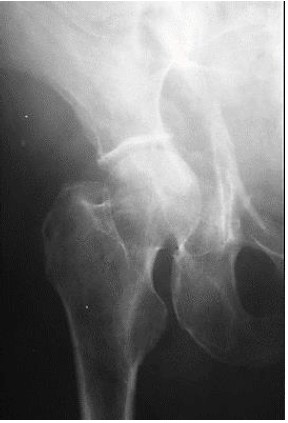

A imagem abaixo mostra:

Provas